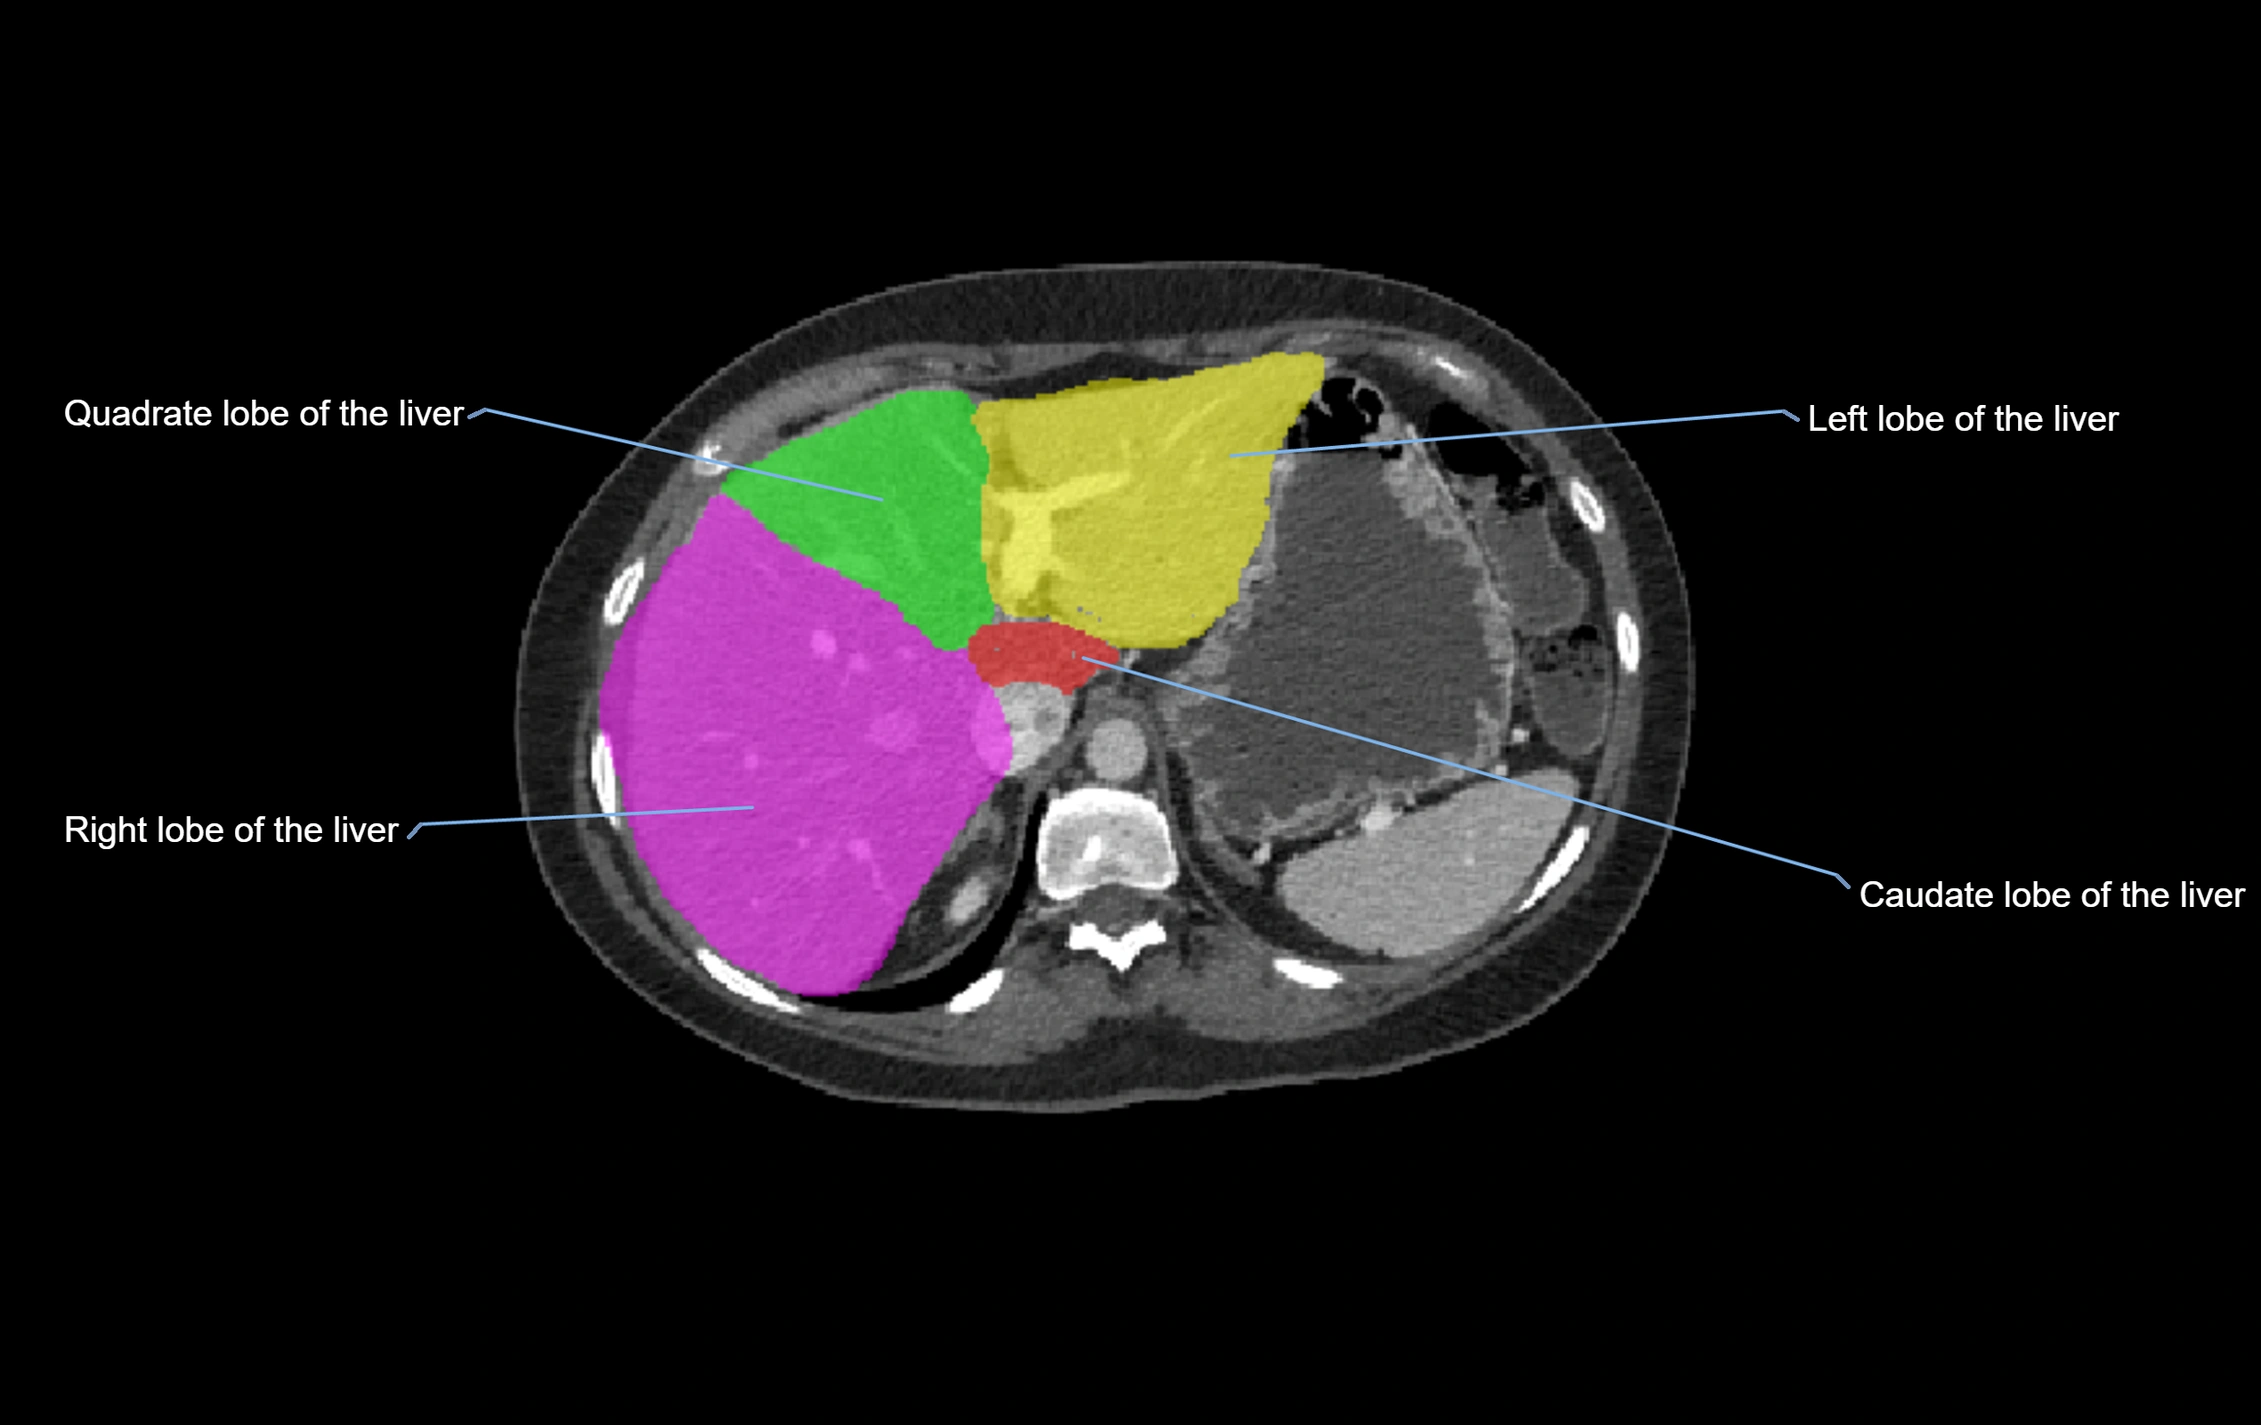

CT Appearance

CT Pre-Contrast:

• Caudate lobe appears as a soft-tissue density, isodense to the rest of the liver

• Enlargement may be appreciated in cirrhosis or Budd–Chiari syndrome

CT Post-Contrast:

• Homogeneous enhancement in the portal venous phase, similar to rest of liver

• Independent venous drainage into the IVC may be visualized

• Lesions follow characteristic CT enhancement patterns (HCC: arterial hyperenhancement with washout; hemangiomas: peripheral nodular enhancement with centripetal fill-in)

CT Venous Phase (functional significance):

• Caudate lobe often enhances relatively more than other lobes in Budd–Chiari syndrome, due to preserved venous outflow

CT Image

image